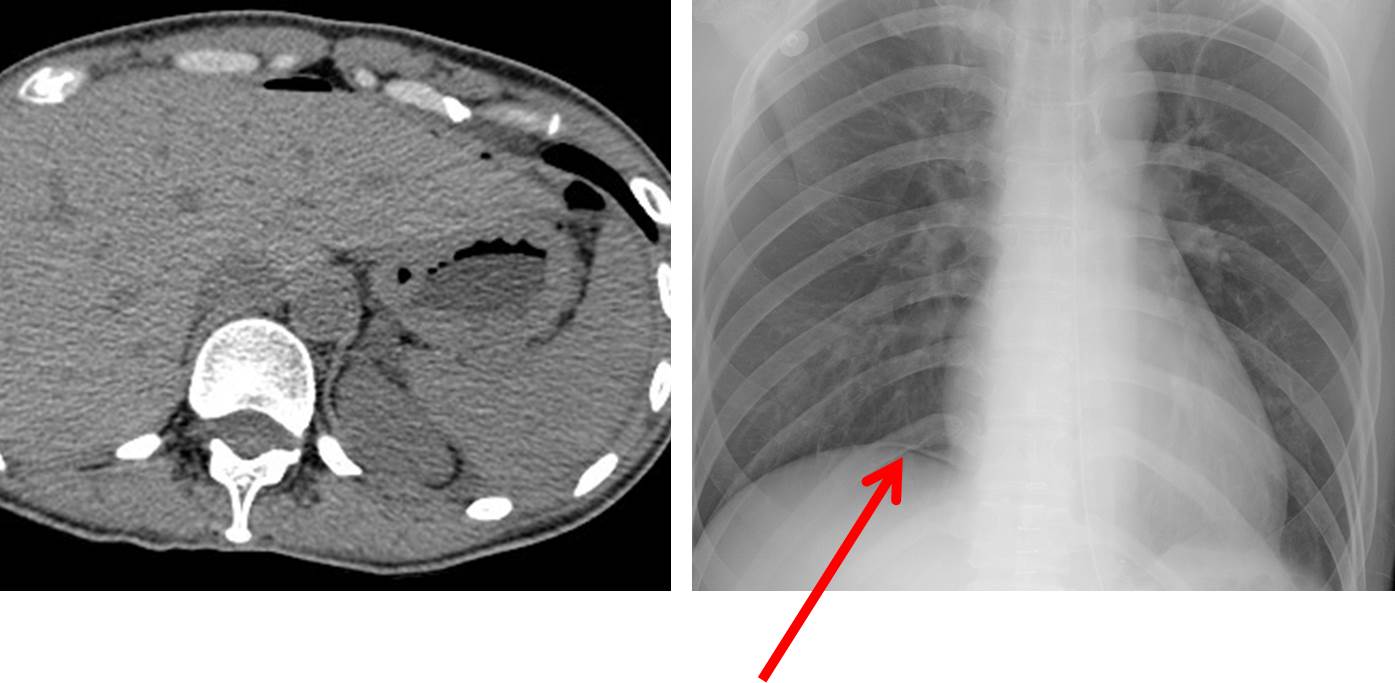

À§¸²ÇÁÁ¾ Ç×¾ÏÄ¡·á µµÁß¿¡¸¸ õ°øÀÌ ¹ß»ýÇÏ´Â °ÍÀº ¾Æ´Õ´Ï´Ù. À§¼±¾Ï(gastric adenocarcinoma) Ç×¾ÏÄ¡·áµµ õ°øÀ» ÀÏÀ¸Å³ ¼ö ÀÖ½À´Ï´Ù. Signet ring cell carcinoma¿´´Âµ¥ XP 3 cycleÈÄ Ãµ°øµÈ ¿¹ÀÔ´Ï´Ù.